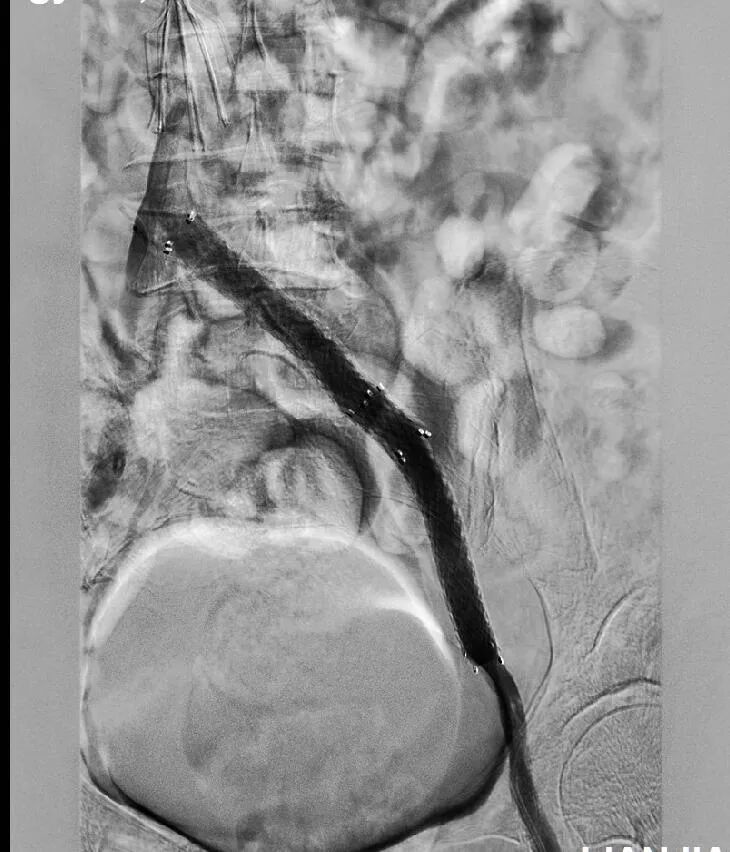

左腘、股、髂静脉多发血栓形成,血流中断

4月23日,在广东医科大学附属医院血管外科副主任医师许托的指导下,创伤外科副主任医师陈国政团队联合介入科团队顺利为患者完成下腔静脉造影、滤器置入和左腘静脉置管溶栓、造影术,4天后又进行了左腘静脉造影、左髂静脉狭窄球囊扩张术、支架成形术。两次手术后,患者左下肢肿胀明显消退,不日康复出院。

术后左股丶髂静脉血栓消失、血流通畅